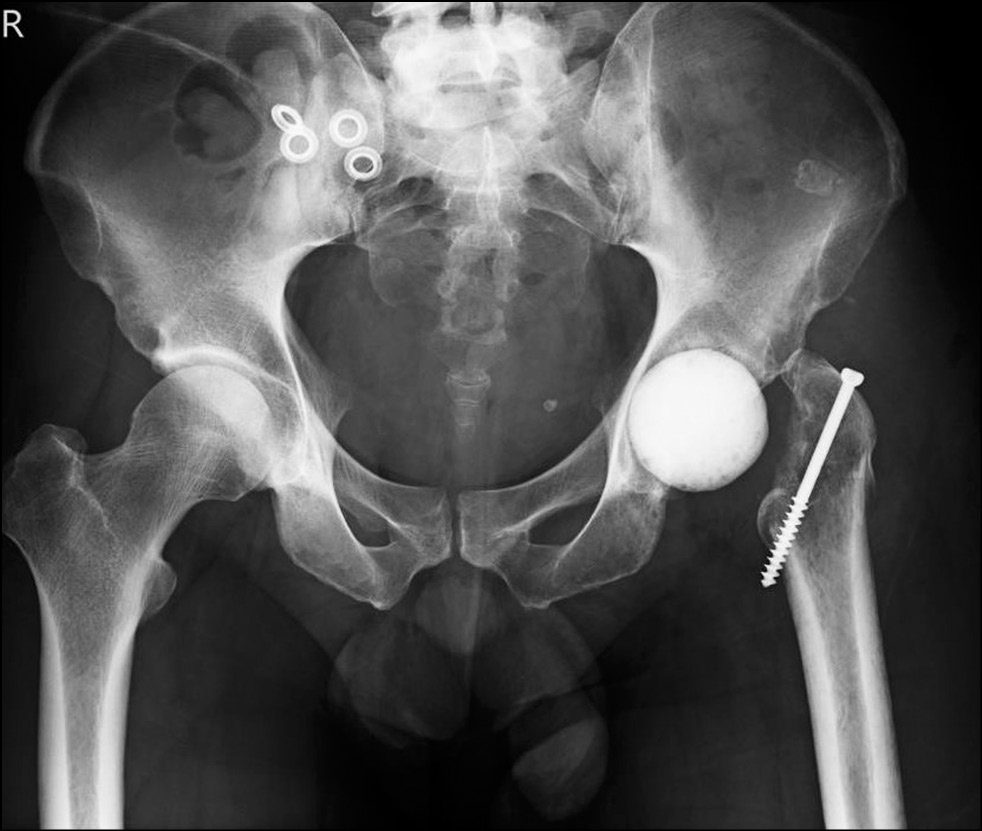

На фоне эмпирической антибактериальной терапии было отмечено снижение уровня лабораторных показателей маркеров воспаления — СРБ, количества лейкоцитов, уровня прокальцитонина. В процессе лечения пациент был консультирован травматологом-ортопедом, которым был поставлен диагноз — асептический некроз головок бедренных костей: слева — III степени, справа — I степени (по ARCO). Вторичный остеоартроз тазобедренного сустава III степени (Kellgren–Lawrence) (рис. 1).

Рис. 1. Рентгенограмма тазобедренного сустава пациента С., 38 лет, в прямой проекции до операции.